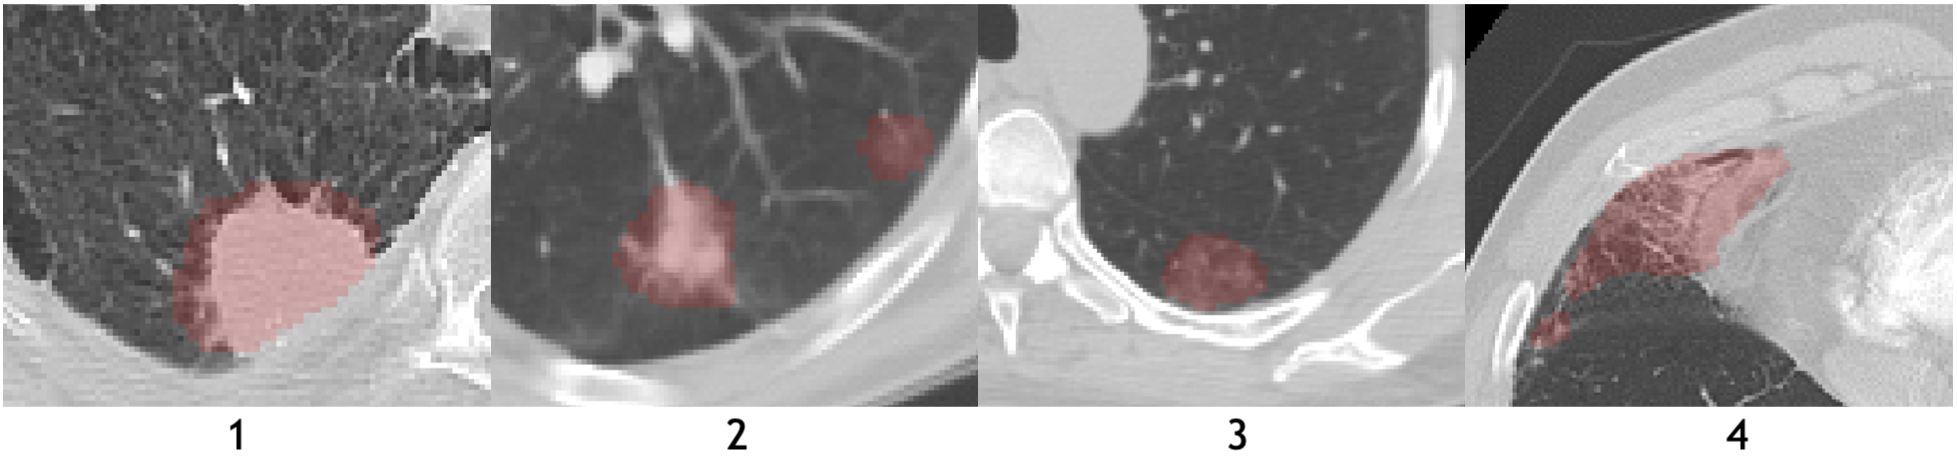

Refer to caption

Figure 2: The axial planes of chest CT scans from three different sites. Areas inside green contours represent COVID-19 affected regions annotated by radiologist. The appearance of the affected region identified as “infiltrates” range from diffused ground glass opacity (COVID, upper row) to focal nodules (lower row).

Nowadays, machine learning based methods have been developed for medical imaging data acquisition, segmentation, and diagnosis of COVID-19 [16, 53]. Relying on the success of deep learning in medical image analysis, imaging characteristics of COVID-19 have been studied and analyzed from various perspectives. Some examples of affected regions of COVID-19 is given in Fig. 2. For the identification and segmentation of such regions, there are two major research directions using deep neural networks. The first one is to use classification models to distinguish normal subjects and patients. Class activation maps (CAM) can be extracted from these models that correspond to the affected region inside the lung area [3, 30, 39, 58]. The second direction is to apply 3D segmentation networks, typically fully convolution networks (FCN), and directly extract the COVID-19 affected regions following an image-to-image fashion [19, 25, 35, 50, 62, 68, 69] shown in Fig. 3.